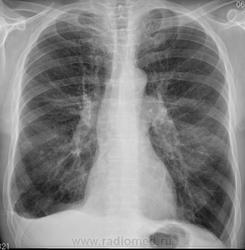

М-да! Что-то по этой ветке я в глухой оппозиции. Всё иначе вижу. Пациент страдает ХНЗЛ со всякими там пневмосклерозами. Переболел плевритом (ранее), после которого остался облитерированный правый синус. Иммунитет, естественно, никакой. Сейчас у него (пока безуспешно) лечится абсцесс в язычковых сегментах.

имхо: абсцесс в S5 слева, вероятно имеет неспецифическую этиологию. Однозначно, был выпот в плевральной полости справа ( не исключаю, что он есть и сейчас).Согласен с коллегами, что не совсем понятно, лечили ли пациента, а если лечили 4,5 месяца то от чего? И какой же рабочий диагноз у клиницистов сейчас?Хотелось бы всё-таки, знать возраст пациента ( дело в том, что так у молодых (до 30 лет) может проткать первичный тубекулёз-сначала плеврит, через несколько месяцев рентенологически проявлются лёгочные изменения при туберкулёзе).

Справа-то всё ушло.Не было туберкулёза,хоть и похоже.Слева-абсцесс.Гадаем о возбудителе.

Слева положительная динамика наметилась, а вот справа появлось что-то новое, пока похожее на воздушную кисту. Интересно, во что это выльется